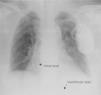

At two-month follow-up post-implantation, atrial detection and capture were absent and the ventricular threshold was three times the implant value. Ventricular sensing was preserved. The patient denied conscious manipulation of the device pocket and reported that she had noticed spontaneous rotation of the device. This was corroborated by the family.

A chest X-ray showed that the generator had rotated and that both leads had become displaced, with the atrial lead situated in the left subclavian vein (Figure 2). Surgery was performed to reposition the ventricular lead and to replace the atrial lead with an active fixation lead (Figure 3); the generator was attached to the pectoral muscle. Subsequent follow-up was unremarkable.